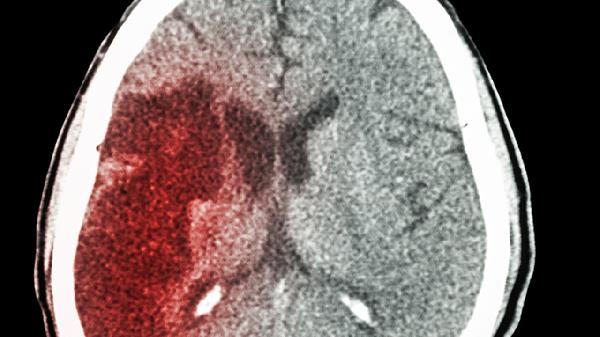

脑出血后四十余天,患者可能仍处于恢复期,脑血管状态尚不稳定。此时若出现感冒症状,如流涕、咳嗽等,部分感冒药物中含有的成分可能对血压、凝血功能或神经系统产生影响。例如某些复方感冒制剂中的伪麻黄碱可能引起血压升高,增加脑血管负担;非甾体抗炎药如布洛芬可能影响血小板功能,不利于出血风险的管控。在这种情况下,自行服用感冒药存在潜在风险,可能干扰脑出血的恢复进程,甚至诱发脑血管事件。患者应先咨询神经内科或康复科医生,由医生评估当前神经功能、血压控制情况及凝血状态,再决定是否需要药物干预以及选择何种安全的感冒缓解方案。